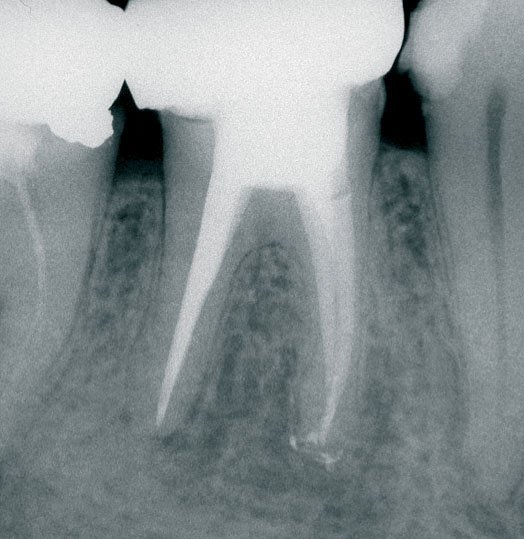

Traitement de canal

Retraitement endodontique

Urgences endodontiques

Traitement des infections périapicales